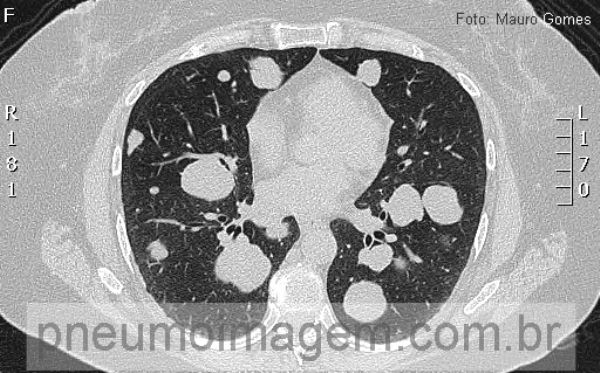

Metástases em bala de canhão. Opacidades arredondadas bilaterais, com limites bem definidos, algumas se superpondo.

Metastases in cannonball. bilateral rounded opacities with well-defined limits, some superimposing.

As lesões se estendem desde os ápices até as bases pulmonares. Os pacientes com tumores de parótida possuem prognóstico melhor que aqueles com tumor de glândula submandibular. O carcinoma mucoepidermóide é o tipo histológico mais prevalente na parótida.

The lesions extend from the apices to the lung bases. Patients with parotid tumors have a better prognosis than those with submandibular gland tumor. The mucoepidermoid carcinoma is the histological type most prevalent in the parotid.

As lesões se estendem desde os ápices até as bases pulmonares. Metástase à distância é um fator de mau prognóstico e ocorre aproximadamente em 20% dos pacientes com tumores primários de parótida. O sítio preferencial é o pulmonar. Nos casos de tumores de glândulas submandibulares, essa taxa atinge 40%.

The lesions extend from the apices to the lung bases. Distant metastasis is a poor prognostic factor and occurs in approximately 20% of patients with primary parotid tumors. The preferred site is the lung. In cases of tumors of the submandibular glands, this rate reaches 40%.